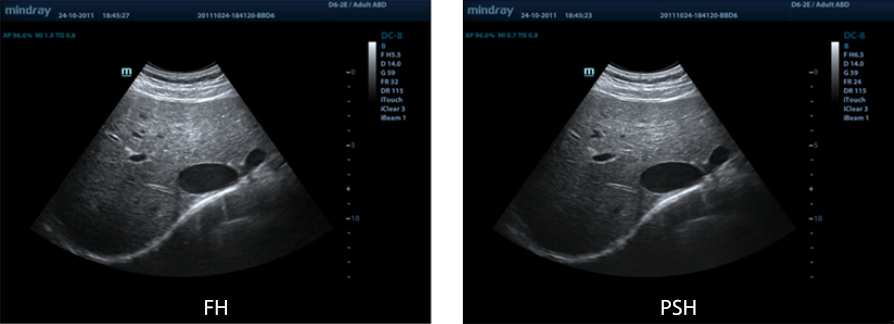

PSHI?(Phase Shift Harmonic Imaging)

Immagine armonica purificata per una risoluzione con miglior contrasto, per fornire immagini pi├╣ chiare con una risoluzione eccellente e meno rumore.